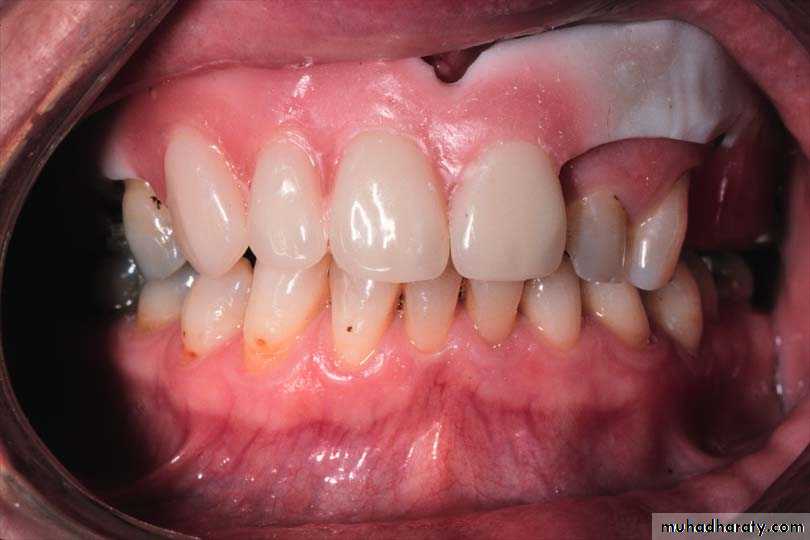

4 . Esthetic are maintained by placing the artificial teeth in a position similar to natural teeth or improved by changing the position.

1. Conventional Immediate Denture (CID): A complete or removable partial denture or overdenture fabricated for placement immediately after the removal of natural teeth. The posterior teeth would be extracted and allowed to heal before the anterior teeth extraction The denture is intended to be relined to serve as the long—term prosthesis.

For patients with periodontally weak teeth indicated for extraction.For socially active people who are very self conscious about their appearance.